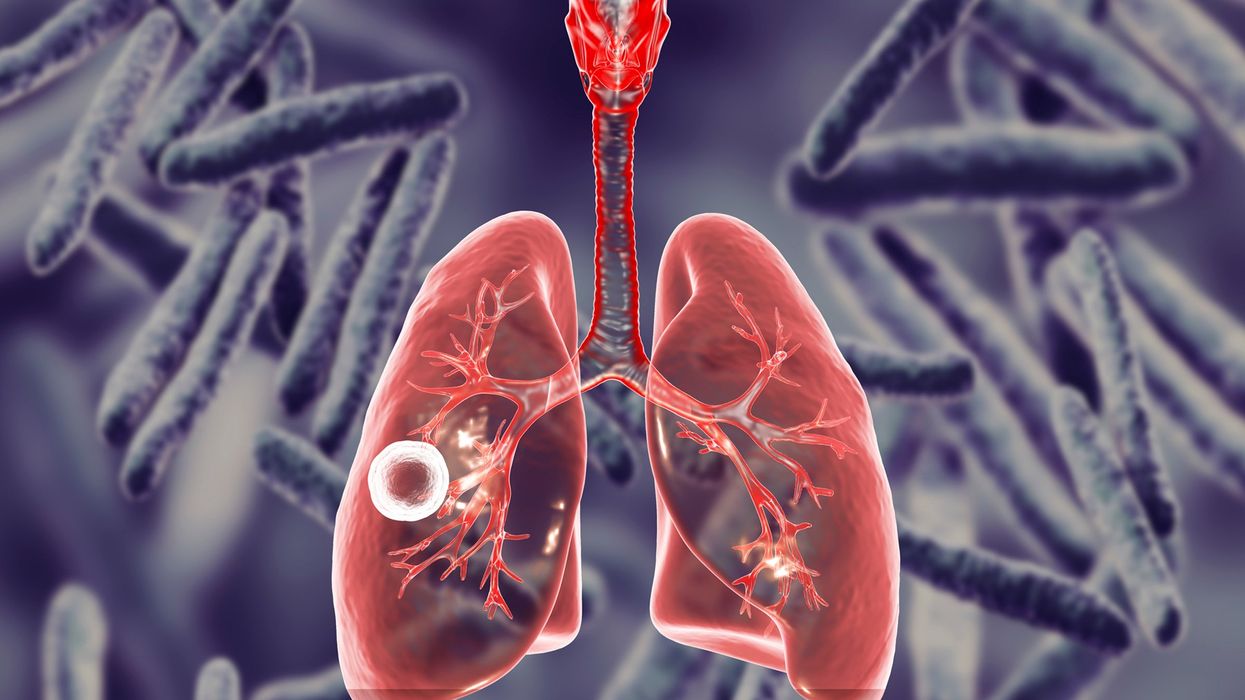

Tuberkulozi është një infeksion bakterial, i cili prek kryesisht mushkëritë, por gjithashtu mund të prekë barkun, gjëndrat, kockat dhe sistemin nervor.

Tuberkulozi, i cili prek mushkëritë, është lloji më i zakonshëm dhe më ngjitës i tuberkulozit. Megjithatë, ajo përhapet vetëm pas ekspozimit më të gjatë me dikë që ka sëmundjen. Në shumicën e njerëzve të shëndetshëm, sistemi imunitar i trupit do të luftojë kundër infeksionit dhe do të vrasë bakteret, pa shkaktuar asnjë simptomë.